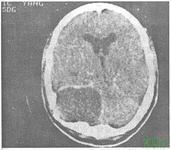

顱內膽脂瘤

顱內膽脂瘤是起源于異位胚胎殘余組織的先天性良性腫瘤,可為多發,無明顯性別差異,任何年齡均可發病,高峰年齡均在40歲。

顱內膽脂瘤的好發部位:好發于腦室或腦池,可延腦室腦池蔓延。最常見的位于小腦橋腦角、鞍旁,也見于第四腦室,側腦室、大腦、小腦和腦干。發生在顱骨橋障和脊柱者約占25%。